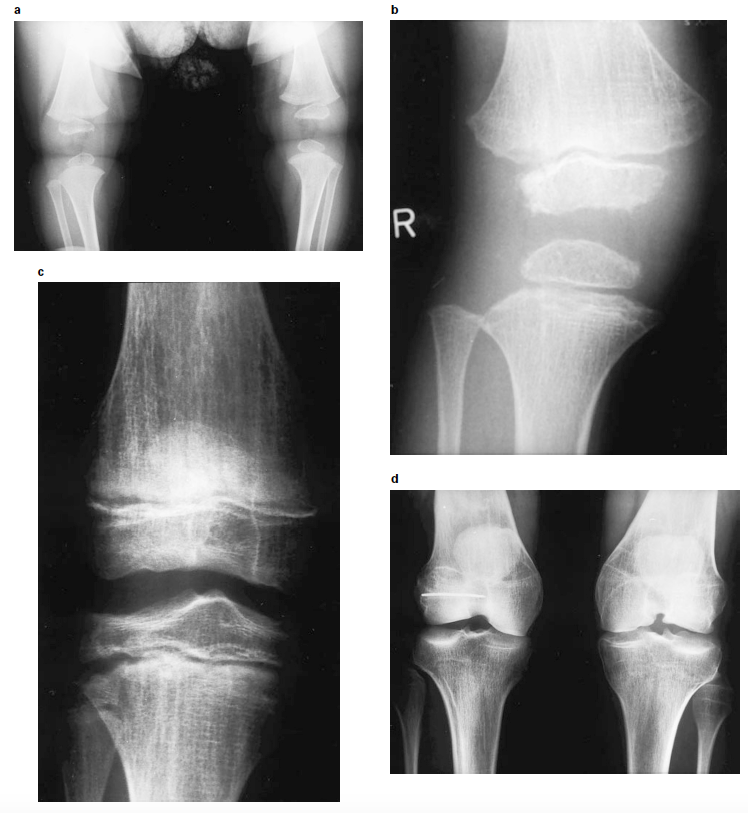

Fig. 2. Radiografias dos joelhos em diferentes idades. a) Joelho de bebé de 8 meses com pequenas epífises com contornos irregulares. (b) joelho aos 5 anos de idade mostra ausência de ossificação da epífise fibular, epífises tibiais e femorais com contornos irregulares (mais pronunciadas na epífise femoral distal), metáfise tibial anómala com defeito de ossificação lateral e borda translúcida e irregular. A metáfise femoral é também irregular com estrias longitudinais. (c) joelho aos 14 anos de idade demonstra epífises achatadas e estrias metafisárias longitudinais, mais pronunciadas na metáfise distal do fémur. (d) Displasia e artrose dos joelhos no indivíduo aos 29 anos de idade. Créditos: European Journal of Human Genetics